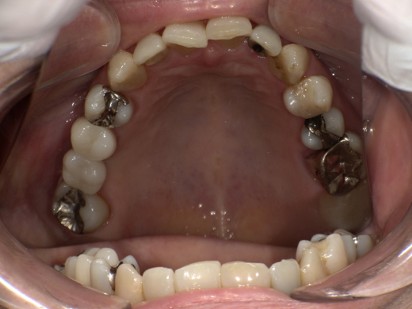

治療前

| 主訴 |

上の左右の奥歯がないのでインプラントについて相談したい。 |

| 治療内容 |

上の奥歯に4本のインプラントを埋入する計画を立てました。 右上は骨の厚みが足りないためCGF(骨再生材料)を用いてソケットリフト(副鼻腔の粘膜も持ち上げて骨の高さを作る処置)を行いインプラントを埋入しました。左上5番は歯根破折のため抜歯して即時に2本インプラントを埋入しました。ご本人の希望で上記処置を1日で行いました。1時間30分程度の時間を要しましたが、ご本人の頑張りもあって無事手術を終える事ができました。 4カ月経過後にインプラントと骨が適切に付着しているか確認し、ジルコニアの上部構造を装着しました。 |